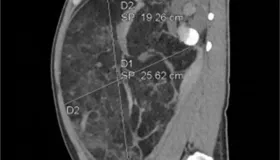

医讯网:33岁男子腹痛就医,竟查出篮球大肾错构瘤破裂大出血!

技术前沿 医讯网:33岁男子腹痛就医,竟查出篮球大肾错构瘤破裂大出血!

互联网医院 医讯网,根据天眼新闻报道得知,33 岁的张先生怎么也没想到,一次突如其来的腹痛,竟让他直面生死考验…